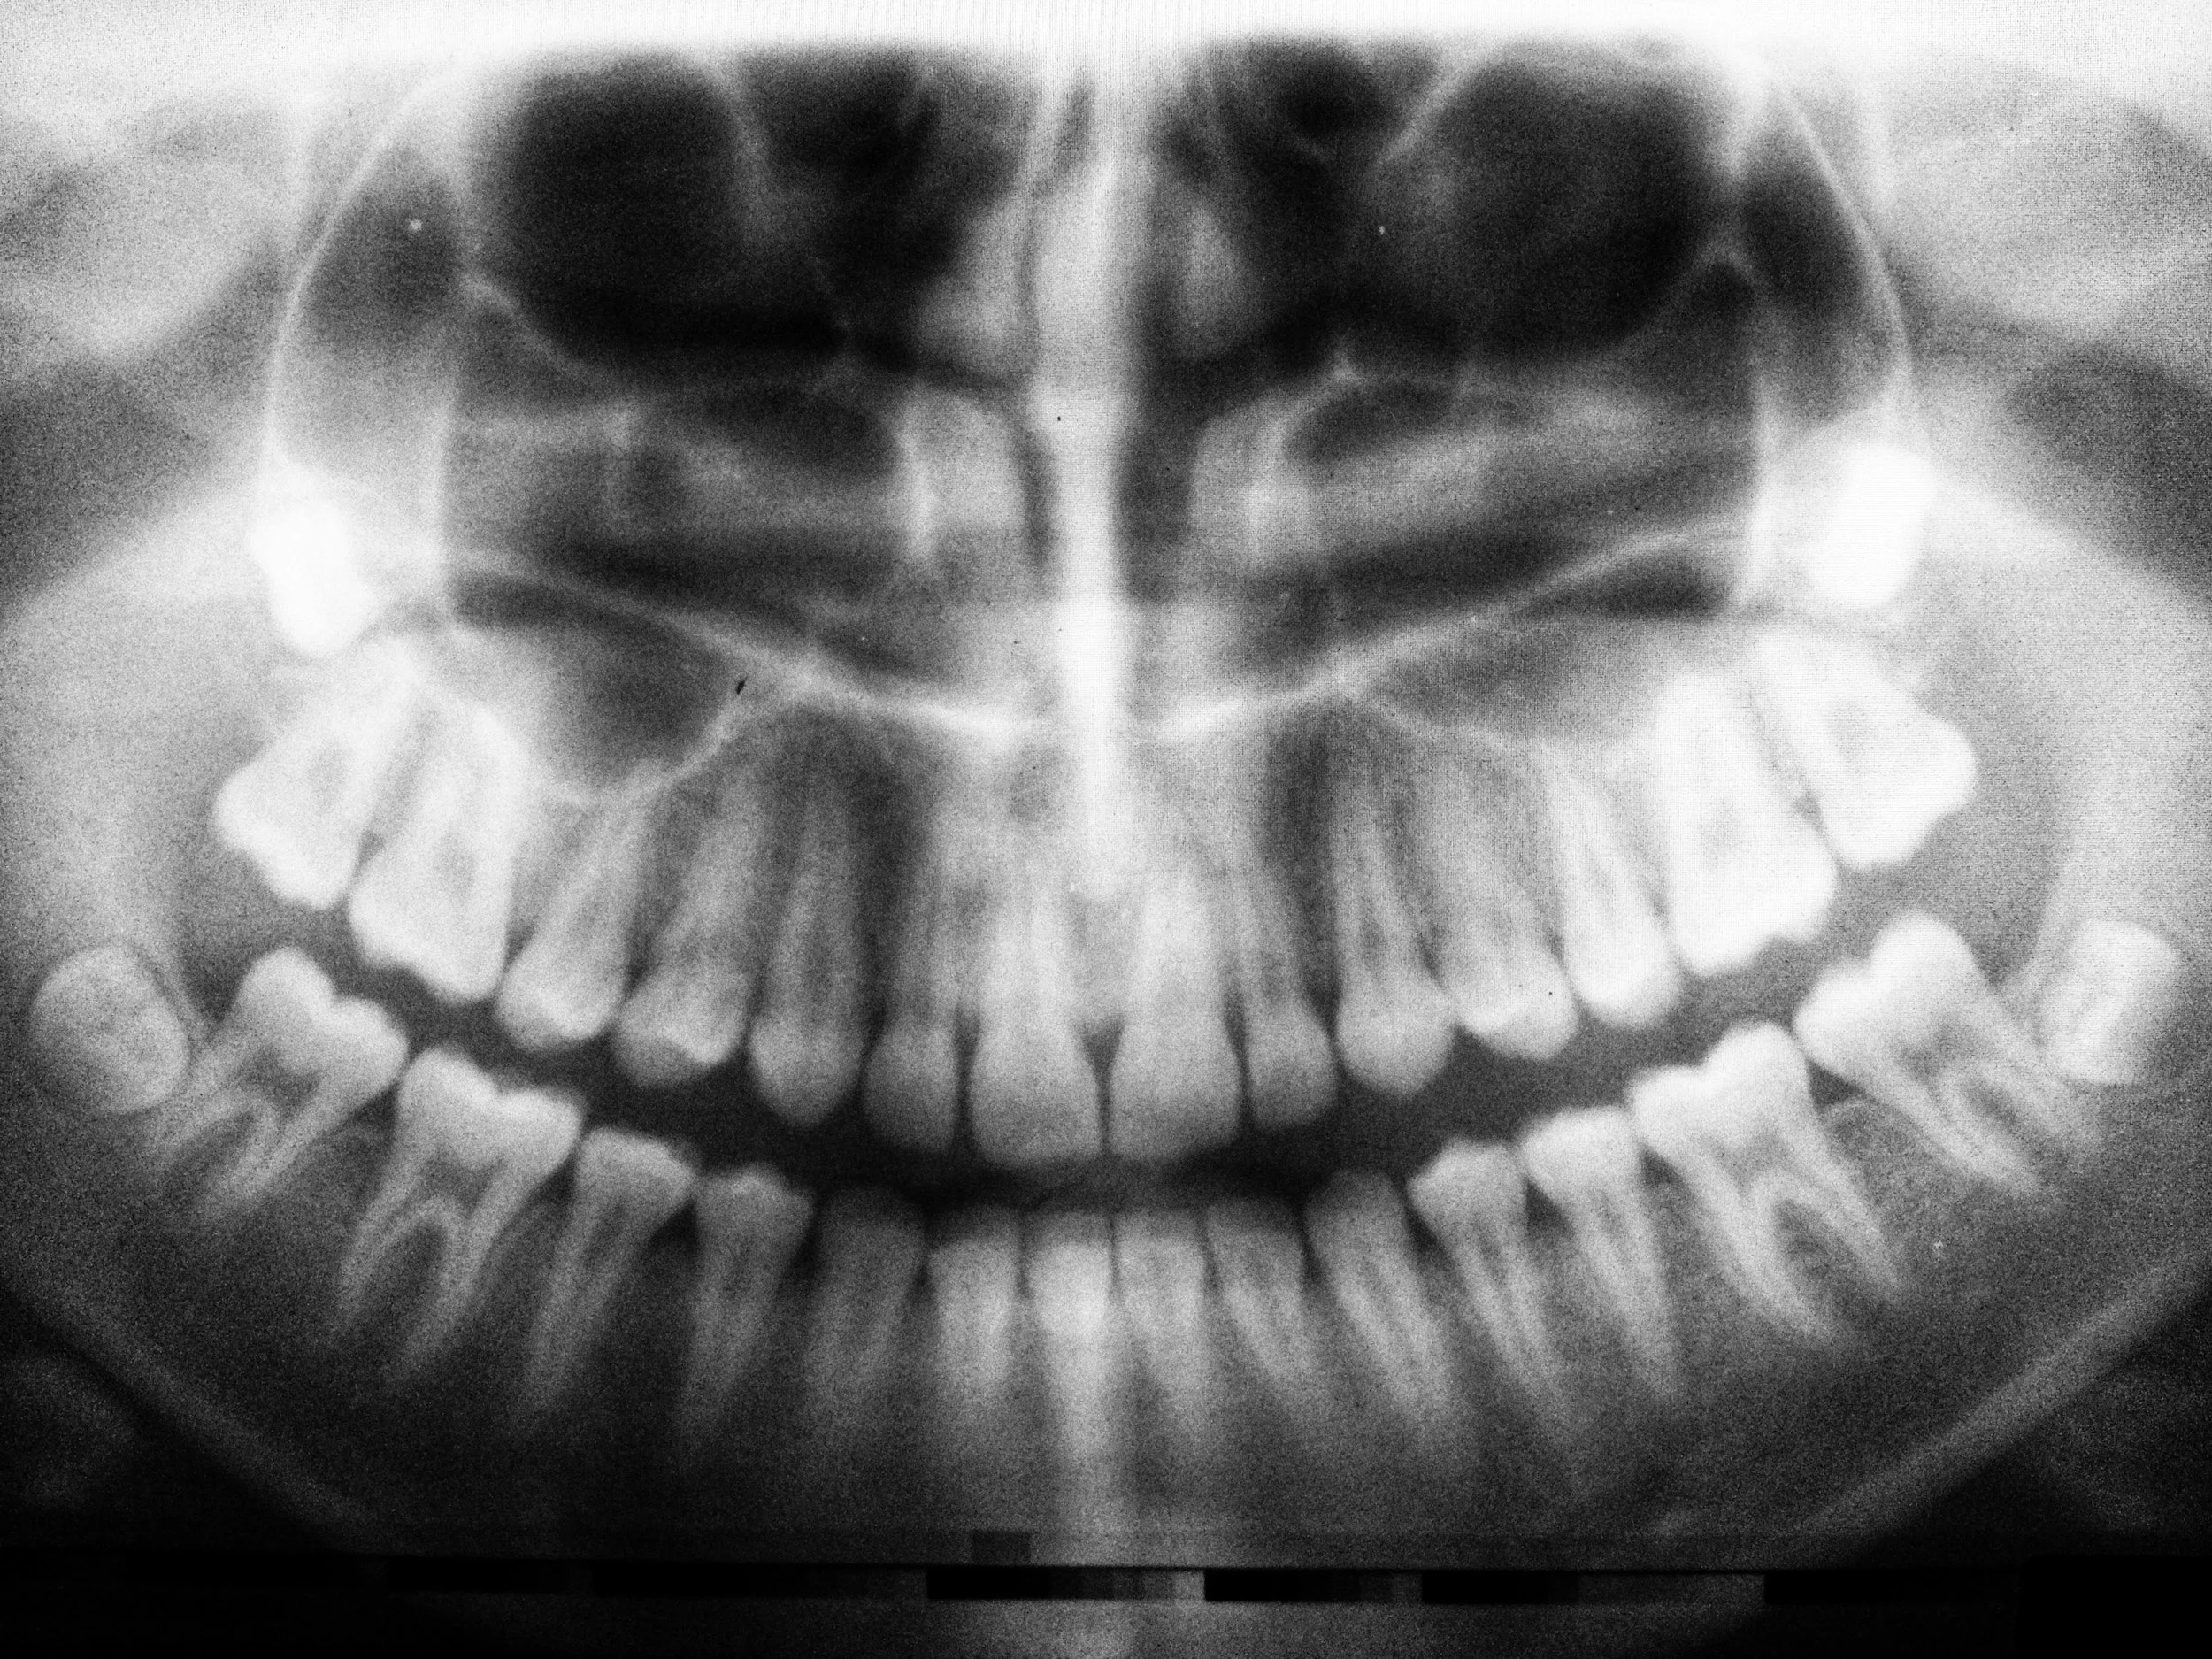

Could your oral health affect Alzheimer’s risk?

Researchers are increasingly exploring how problems in the mouth, such as gum disease and chronic inflammation, might influence brain health. Certain oral bacteria and inflammatory signals may enter the bloodstream and potentially contribute to processes linked with cognitive decline, though the science is still developing and doesn’t prove cause-and-effect. What’s clear is that good oral hygiene is a low-risk, high-reward habit. Brush gently with fluoride toothpaste, floss daily, clean your tongue, and keep up with regular dental visits.